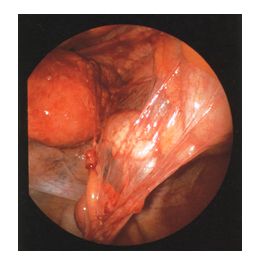

右の写真は、実際に腹腔鏡で腹腔内を観察したものです。

子宮と卵管、卵巣、そして腸管との間に膜状の癒着が起こっているのがはっきりとわかります。

このような癒着は子宮内膜症、子宮付属器炎(クラミジア、淋病、大腸菌や結核菌などが原因となって起こる卵管や卵巣などでの炎症性疾患)などでよく見られるものです。

超音波や内診では、なかなかこのような癒着を発見することはできないもので、腹腔鏡を行ってみて初めてわかるものと言っても良いでしょう。